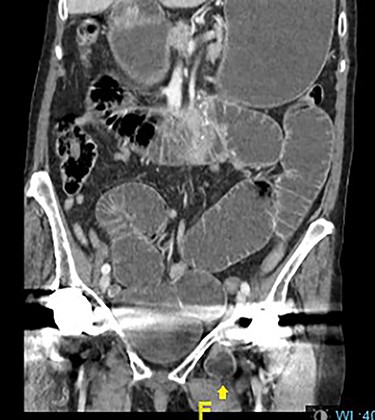

On initial presentation, her blood results were as follows: white cell count (WCC) 14.8 × 109 cells/l (RR 4.3–11.2 cells/l), neutrophils 12.3 × 109 cells/l (RR 2.1–7.4 cells/l) and C-reactive protein (CRP) 1.9 mg/l (RR 0–5 mg/l). Imaging performed included an abdominal film, which showed nonspecific bowel gas pattern (Fig. 1). The patient was managed conservatively and discharged home. She represented 2 days later with worsening symptoms and blood results of WCC 20.1, neutrophils 18.4 and CRP 6. She was admitted under the surgical team and a thoracic and abdominal CT scan was done (Figs 2–4). It was initially reported as significant dilated small bowel loops in keeping with small bowel obstruction due to a femoral hernia. However, the scan was revisited by the surgical team in more detail as the images appeared to represent an obturator hernia. Upon further discussion, these findings were corroborated by the radiologist and a strangulated left obturator hernia was identified.

Distended stomach and dilated bowel loops with an obturator hernia (pointed by the arrow), as shown in the coronal section.